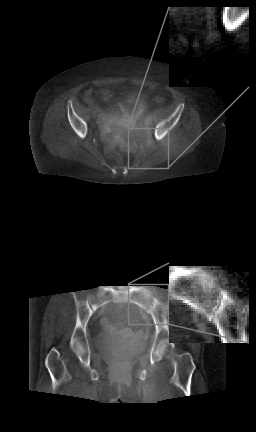

Refer to caption

(a)

(b)

(c)

(d)

Figure 4: (a) Axial (top) and coronal (bottom) slices of planning pelvice CT, HU range=(-400, 400) and (-150, 250) for ROI, (b) FDK (c) TV++ (d) LIRE++

We perform a proof-of-concept evaluation of LIRE++ on real CBCT pelvic data and compare it to the FDK baseline with U-net for scatter pre-correction and a proprietary TV++ method currently in use in our center. In addition to FDK we evaluate its calibrated version, where the HU values from FDK reconstruction all undergo a single affine transformation, which was determined by a linear regression matching central slices of the FDK reconstructions with the corresponding slices of planning CTs. To provide quantitative a comparison in terms of HU accuracy, we used planning CT and rigid registration.

The results are presented in Table 2. MAE in Hounsfield Units is measured in the central full field of view region. Additionally, we selected four spherical regions of interest between 2 and 4 cm in diameter, which are well aligned in planning and CBCT, and computed the mean HU intensities inside these regions to measure reproduction accuracy of various regions. The mean difference of these HU averages between planning CT and the reconstructions are given in Table 2 as well. Axial and coronal image slices are presented in Figure 4.

This comparison demonstrates that LIRE++ translates well to real CBCT pelvic data. Reconstruction given by LIRE++ is noticeably cleaner than the TV++ reconstruction, scatter artifacts in particular are well-suppressed. Field of view given by LIRE++ is slightly larger compared to TV++. We have measured an improvement in mean HU accuracy, however, due to anatomical differences such comparison can underestimate actual reconstruction quality. TV++, on the other hand, substantially outperforms a classical FDK method with deep-learning scatter precorrection and its calibrated version.